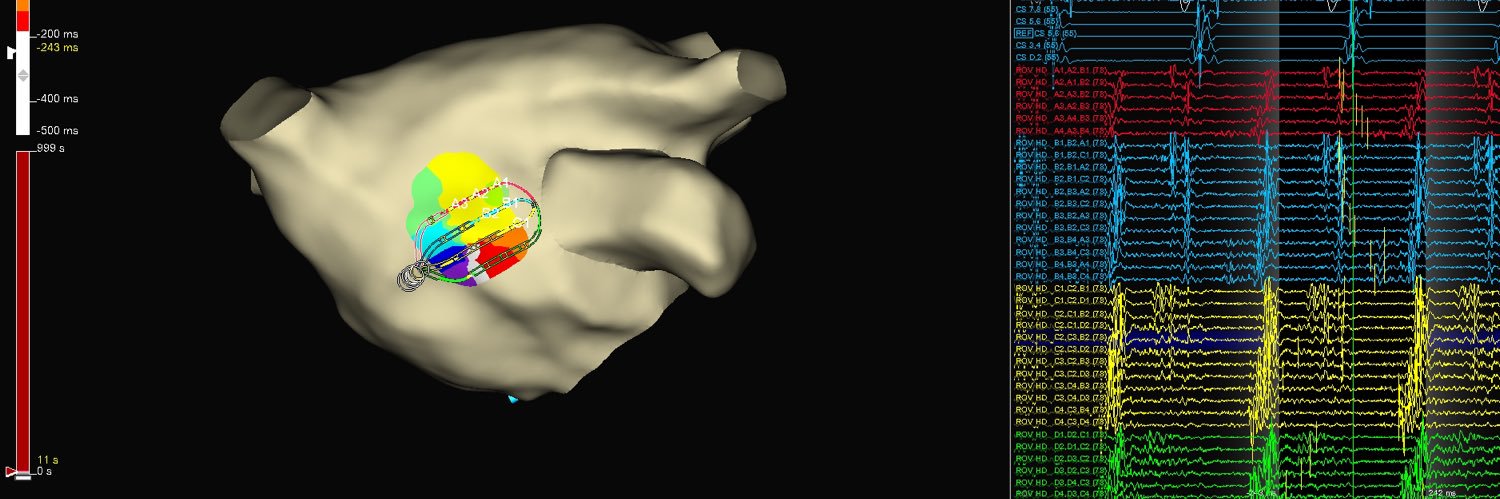

First AP case on #EnSiteX using #OT with @Segarspr did not disappoint. OT Vectors beautifully highlight activation funneling down this antegrade left lateral AP. #HDGrid @AbbottCardio

In the lab with @docAnneSquared today so you know it’s gonna be good! Shown here RV apical and RVOT pacing open window mapping helping us find this beautiful slanted pathway. One burn to cure! ❤️🔥 Thanks to the OG of mapping @AMatthews0 for these beautiful maps. @MUSC_EP